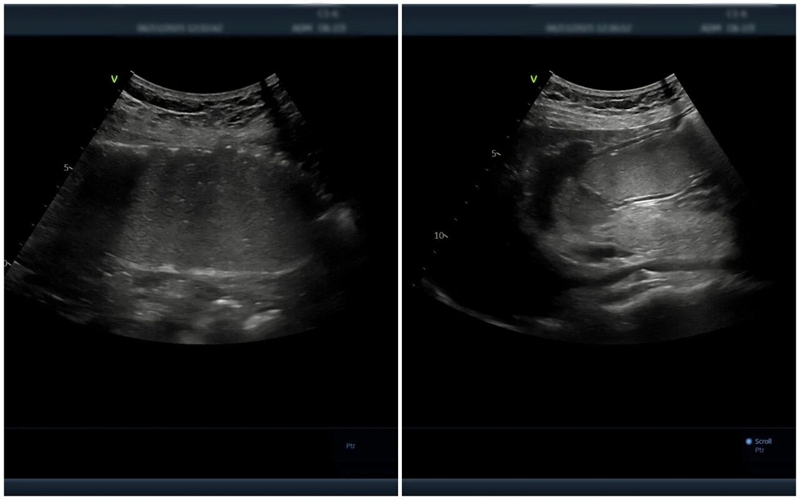

△胃肠超声造影提示:黏膜层毛糙,回声减低,胃壁呈局限性增厚,符合慢性胃炎声像图特征